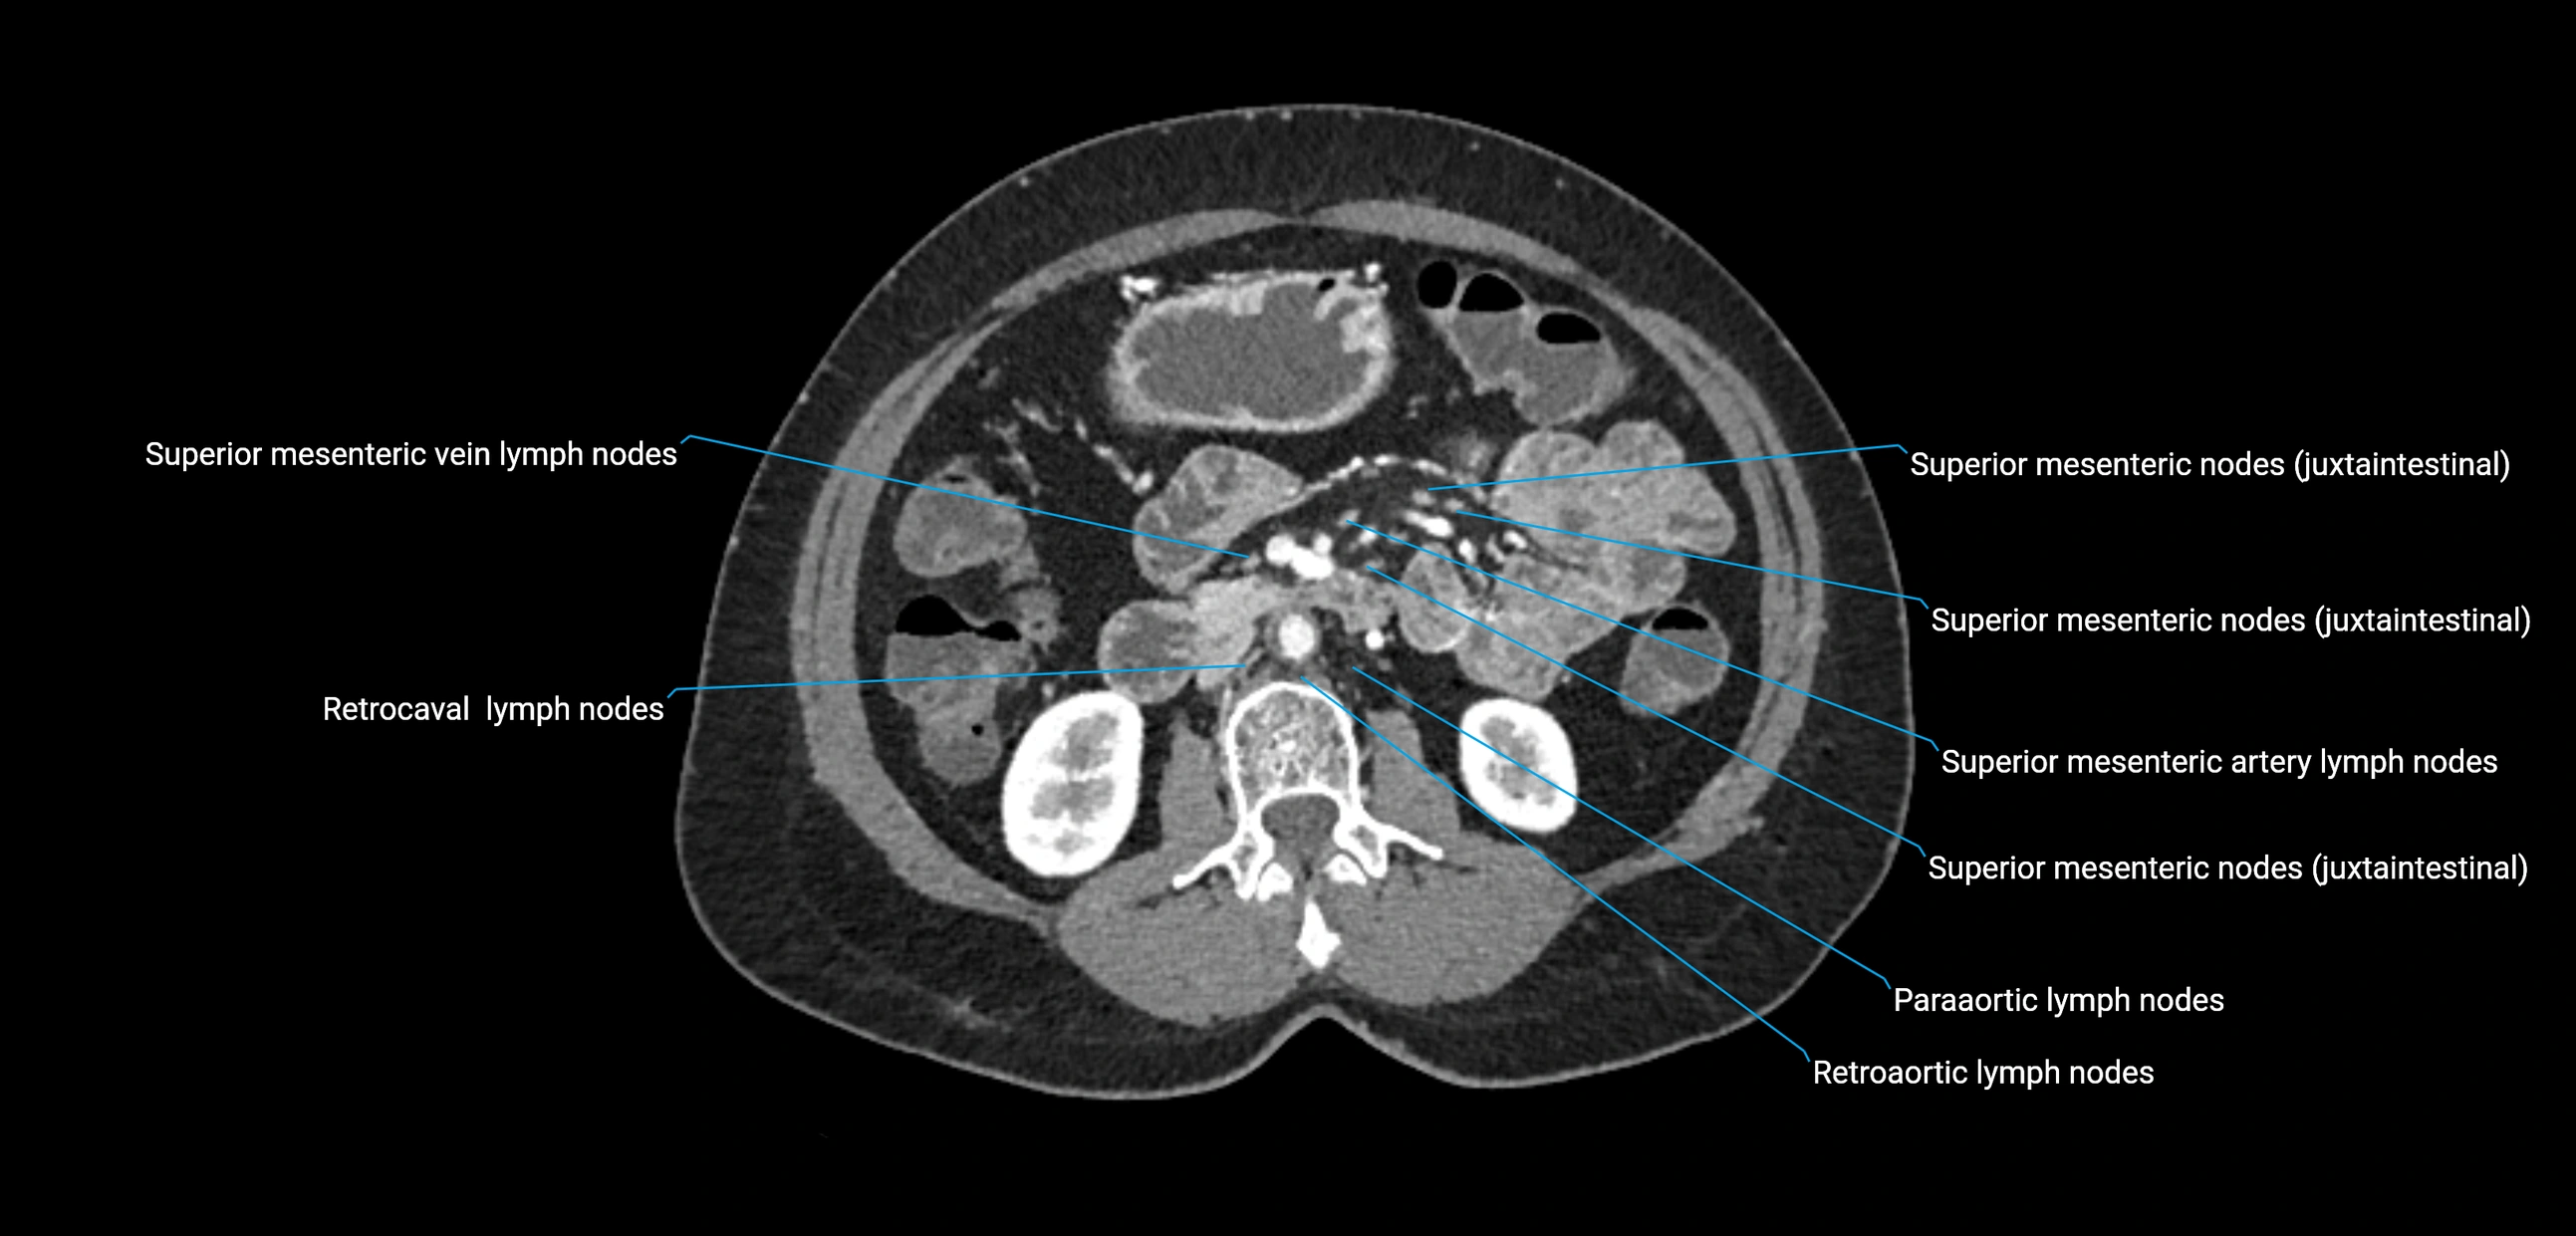

CT image

image